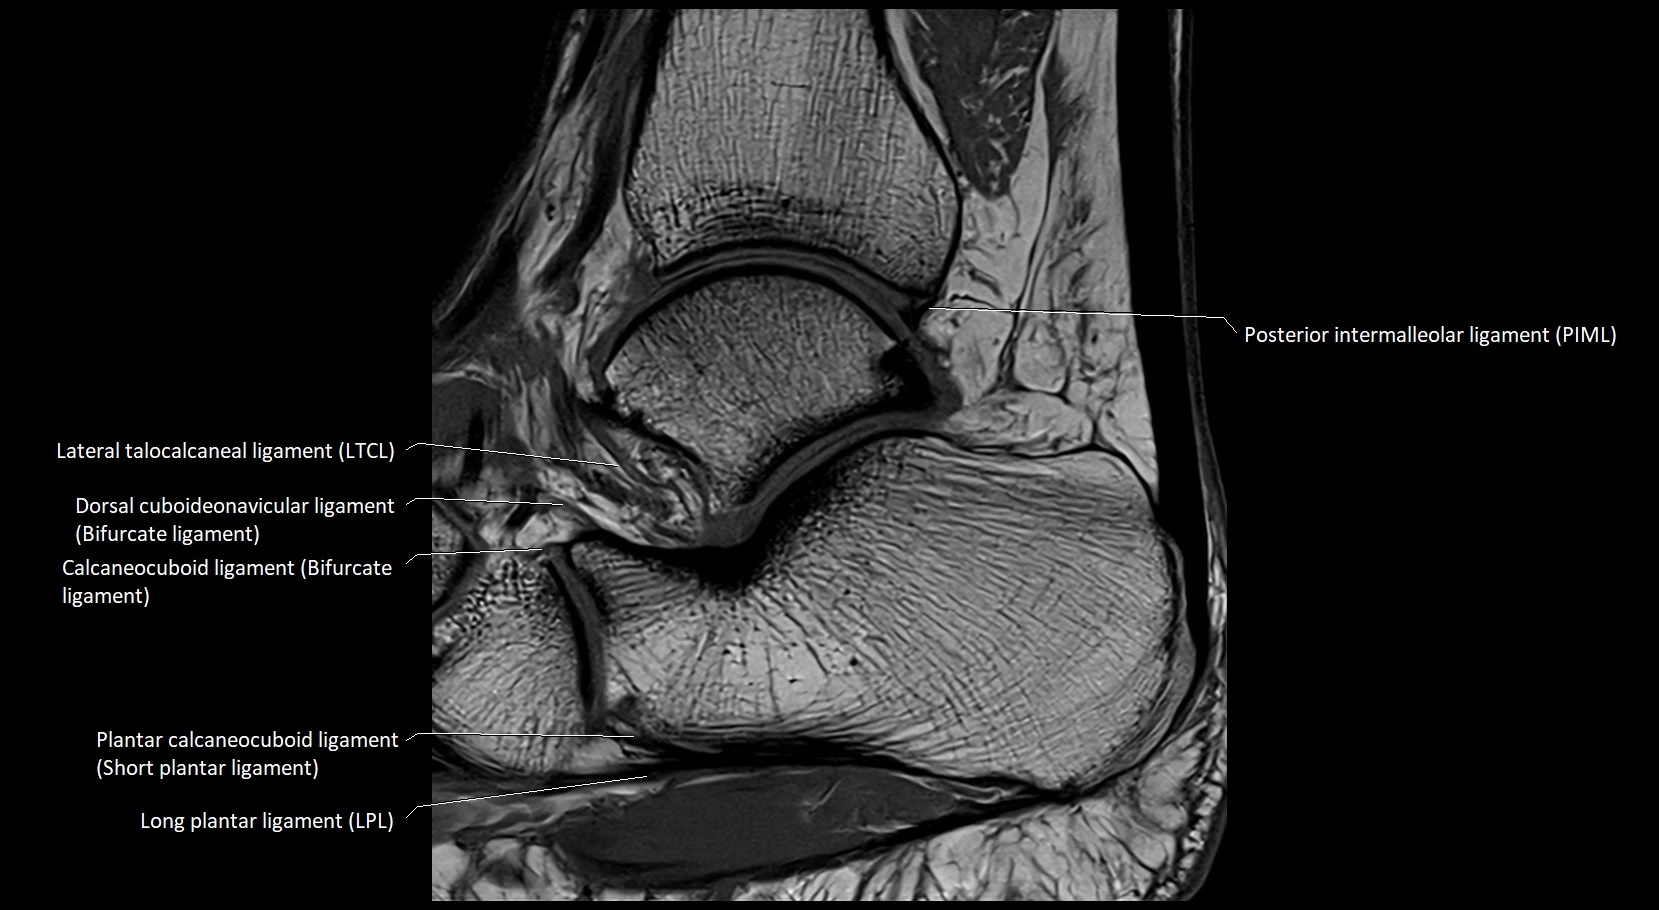

MRI image

image